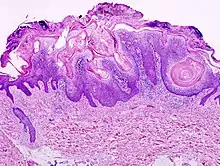

Micrograph of a seborrheic keratosis (H&E stain, scanning magnification)

Visual diagnosis is made by the "stuck on" appearance, horny pearls or cysts embedded in the structure. Darkly pigmented lesions can be challenging to distinguish from nodular melanomas.[8] Furthermore, thin seborrheic keratoses on facial skin can be very difficult to differentiate from lentigo maligna even with dermatoscopy. Clinically, epidermal nevi are similar to seborrheic keratoses in appearance. Epidermal nevi are usually present at or near birth. Condylomas and warts can clinically resemble seborrheic keratoses, and dermatoscopy can be helpful to differentiate them. On the penis and genital skin, condylomas and seborrheic keratoses can be difficult to differentiate, even on biopsy.

A study examining over 4,000 biopsied skin lesions identified clinically as seborrheic keratoses showed 3.1% were malignancies. Two-thirds of those were squamous cell carcinoma.[9] To date, the gold standard in the diagnosis of seborrheic keratosis is represented by the histolopathologic analysis of a skin biopsy.[10]